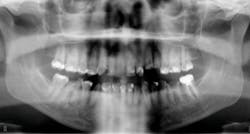

DURING the last few years, some of the greatest innovations in implant designs have occurred in relation to the immediate placement of implants. “Old-school” implant designs generally involved cylindrical, nontapered implant bodies with relatively dull and shallow threads. But modern, more recent implant designs have included tapered implant bodies with sharper, deeper, and more aggressive threads. This has allowed for more engagement in the bone (osseocompatibility), with greater primary stability, which has equated to earlier loading times. These more modern designs have also created greater success rates, which has led to the immediate implant procedure being more popular with general practitioners in the United States.

One of the best ways to practice economical and predictable implant dentistry is to use, when appropriate, immediate placement at the time of extraction. The patient is in the chair and motivated to complete treatment right then. I have found that, with some patients, if you extract the tooth and wait a few months to place the implant, they will sometimes get used to the empty space and procrastinate on having the tooth replaced. The repercussions of not replacing the tooth, such as bone loss, shifting, bite changes, and occlusal overload of neighboring teeth, take time to manifest and are not always readily apparent to the patient. But once these problems are noticed by the patient, the treatment plan often becomes more involved and expensive—and sometimes out of reach financially. Large grafting procedures can also be intimidating to patients, which prevents them from following through with procedures.

Another reason immediate placement is advantageous is that once the extraction is complete, the hole is usually already in the proper place for the implant. You may have to redirect your osteotomy slightly palatally, mesially, or distally, but the socket serves as an excellent guide for placement. In some cases, especially premolars, you can use an implant with aggressive threads to place without any osteotomy at all. You can engage the mesial and distal walls to achieve primary stability. This greatly shortens the appointment time, lowers risk, and increases patient satisfaction. Figures 1 and 2 show a MorsTorq in site No. 21 that was placed after an atraumatic extraction during my most recent two-day Louisiana Implant Institute course. Note the sharp threading on the MorsTorq, which allows for optimized immediate placement performance.There are some circumstances where immediate placement is not desirable. If the socket is too large to engage the mesial and distal walls and vital anatomical structures are located just apical to the socket, immediate placement is not recommended. Chronically infected sites also present a higher risk for immediate placement. If you can completely rid the socket of all soft tissue and the patient has the appropriate antibiotics onboard, it is possible. However, most of these cases are more predictably treated with early placement (waiting four to six weeks without grafting) or delayed placement (three to six months with grafting).